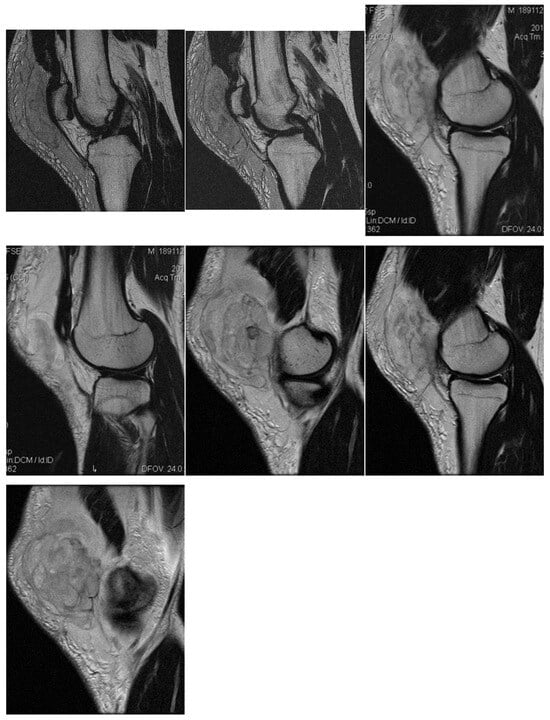

3.1. Case 1: Vastus Lateralis Tear with Prepatellar Hematoma

Right back, 22 years old, national-team player from a rural area, professional first-league athlete, 198 cm, 110 kg. In the initial case, the right back sustained injuries to the knee and the distal portion of the left thigh during a training session, attributed to a lateral concussion and the “opening” of the internal compartment. The clinical examination revealed pain, swelling, edema, a bubble knee, relative functional impairment, and restricted active and passive movement of the left knee. A sprain of the left knee was suspected, with potential damage to the meniscus, cruciate ligaments, and collateral ligaments. Although the MRI did not indicate any damage to the intra-articular structures, it did reveal a substantial prepatellar extraarticular hematoma, resulting from a muscle tear in the vastus lateralis muscle, along with significant edema of the soft tissue. The extraarticular edema is evident in the non-homogeneous Ts and STIR hyperintense, accompanied by T1 hypo- and hyperintense. Post-traumatic edema of the adjacent soft tissue is depicted in STIR as an altered diffused hyperintense (Figure 1, Figure 2 and Figure 3).

Sagittal T2 acquisition.

Knee MRI: axial T2 acquisition.

Knee MRI: coronal stir acquisition.

Treatment consisted of myorelaxant medication, cryotherapy, and local applications of heparin gel in the first stage, followed by physical and kinetotherapy to prevent the hematoma from becoming chronic and infected and regain knee mobility and return to full training after 6 weeks.